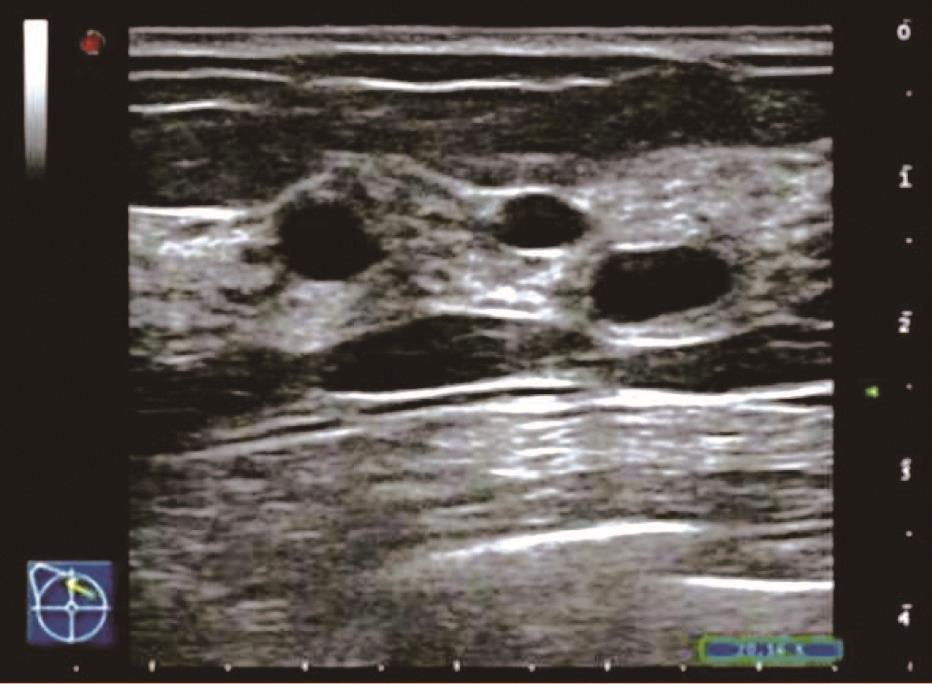

(3)囊性增生型:表现为乳腺组织回声增粗、增强,较杂乱,腺体内可见散在大小不等的圆形或椭圆形囊状无回声或长条形管状无回声区,边界清晰,壁薄光滑,透声好,内部偶见分隔回声带,也可有少许点状回声,内部无明显彩色血流信号。

患者,女,35岁,因双乳疼痛两月,乳头偶有针刺状疼痛,感到胸闷,呼吸不畅来院诊治。超声检查结果显示:右乳内可见多个无回声区,边界清晰,形态规则,其中3点方向较大一个1.7*0.6cm,内可见分隔光带,左乳内可见数个无回声区,边界清晰,形态规则,其中3点方向较大一个大小1.1*0.6cm内可见分隔光带,CDFI探查:未见异常血流信号显示。双侧乳腺切面形态轮廓正常,层次清楚。腺体厚薄不均,边界完整,欠规则,结构紊乱,分布不均,呈片状高回声区。

超声提示:两侧乳腺增生。